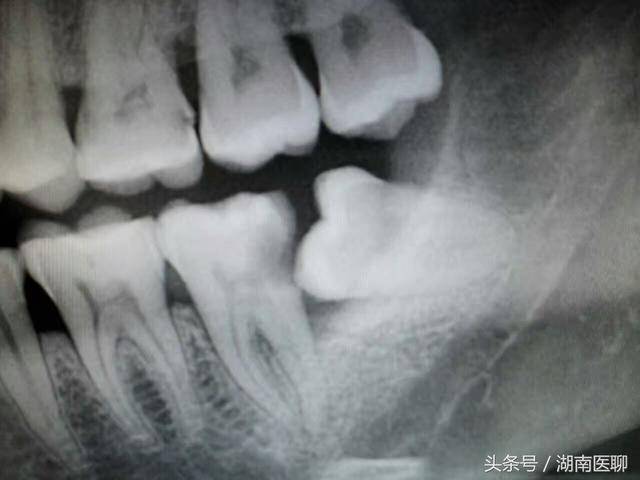

医生:固然你的智齿不痛不痒,但是位置不正,先上两张曲不雅图看看邓旋。

(智齿位置不正)

那别离是右下和左下两颗智齿邓旋,就是因为位置不正,固然它本身没坏,但它把前面的牙齿毁坏出一个大洞,也就是“虫牙”,然后拖着没处置,招致牙髓也传染了,牙髓炎爆发痛得他人不要不要的,你也想尝尝吗?